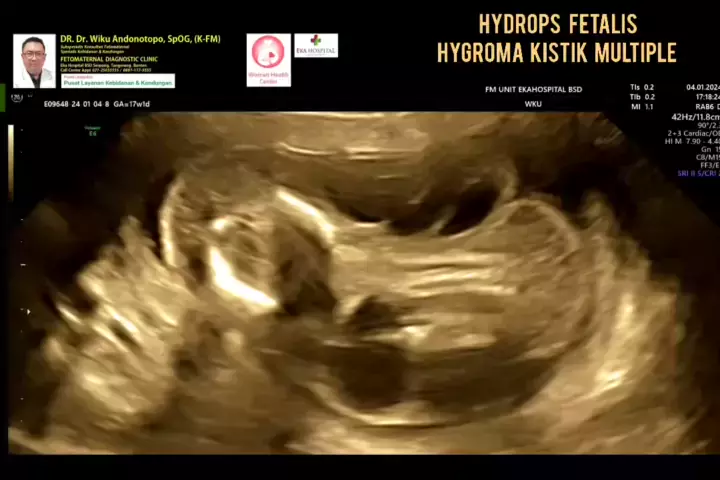

Hydrops Fetalis - Multiple Hygroma Cystic..... #drwikuandonotopo #drwiku_andonotopo #polikandunganekahospitalbsd #fetomaternalekahospitalbsd #usgfetomaternalekahospitalbsd #konsultanfetomaternalekahospitalbsd #ekahospitalbsd #ekahospitalcibubur #ekahospitalbekasi #ekahospitalpekanbaru #fetomaternalbekasi #fetomaternalcibubur #fetomaternalsemarang #fetomaternal #konsultanfetomaternal #usg #usg4d #perkembanganbayi #perkembanganjanin # #melahirkannyaman #melahirkannormal #melahirkancesar #janin...